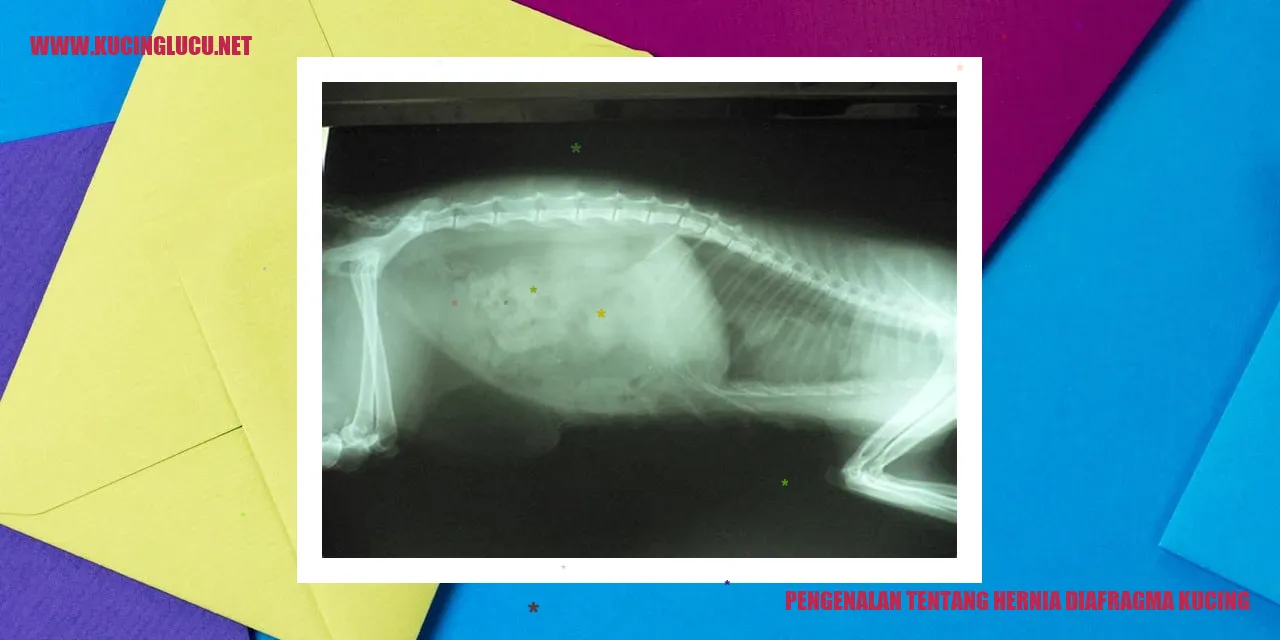

Hernia diafragma pada kucing adalah kondisi medis di mana organ-organ dalam tubuh kucing menonjol melalui lubang alami di diafragma. Diafragma merupakan otot yang memisahkan rongga dada dan perut pada kucing. Terjadi kelemahan atau kerusakan pada diafragma, sehingga organ-organ seperti hati, lambung, usus, bahkan jantung bisa masuk ke rongga dada.

Kondisi hernia diafragma pada kucing adalah kegagalan pada otot yang memisahkan rongga dada dan perut. Kelemahan ini menyebabkan organ-organ perutnya beralih ke rongga dada, mengganggu pernapasannya secara serius.

Hernia diafragma adalah kondisi medis di mana organ dalam perut kucing mendorong melalui celah di otot diafragma, yang memisahkan area dada dan perut. Ras kucing yang paling sering mengalami hernia diafragma adalah Persia, Himalaya, dan Birma.

Hernia diafragma pada kucing adalah kondisi ketika organ dalam dada terjepit melalui celah di otot diafragma; otot yang memisahkan rongga dada dari perut. Hernia diafragma bisa bersifat bawaan atau terjadi akibat cedera atau kecelakaan. Ketika mengalami hernia diafragma, organ dalam seperti usus atau organ perut lainnya bisa masuk ke dalam dada, menyebabkan gejala serius yang membutuhkan penanganan medis segera.